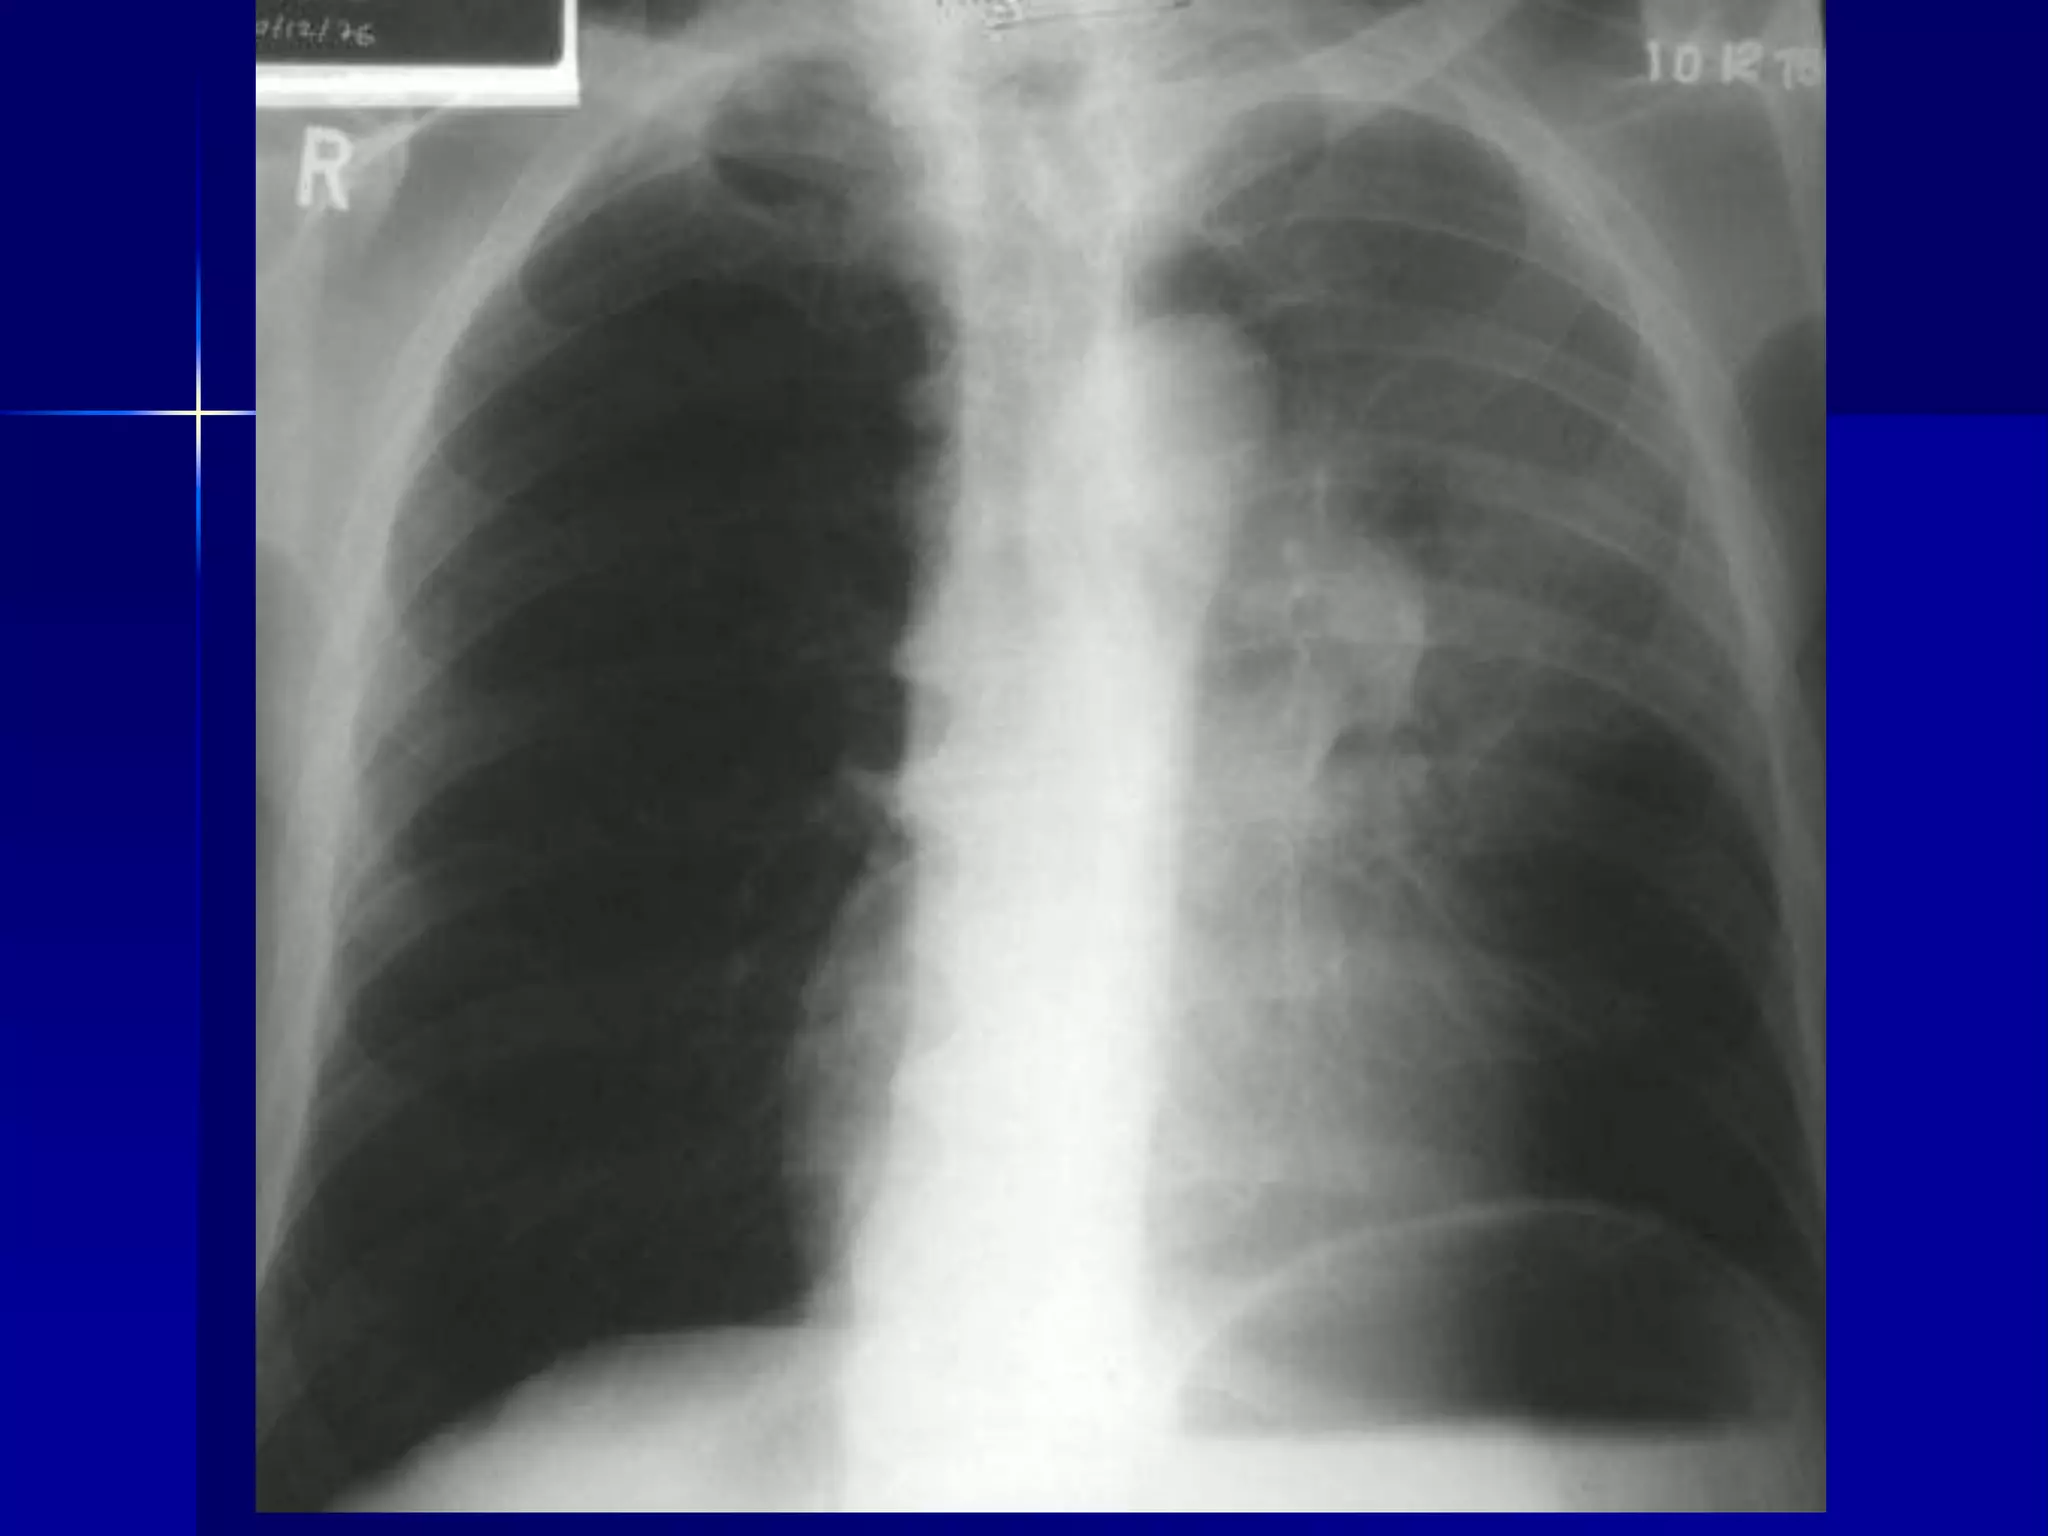

Atelectasis Right Lung

 Homogenous density right hemithorax

 Mediastinal shift to right

 Right heart and diaphragmatic

silhouette are not identifiable

 Atelectasis Right Lung

 Open Bronchus Sign

 Right heart and diaphragmatic silhouette

are not identifiable